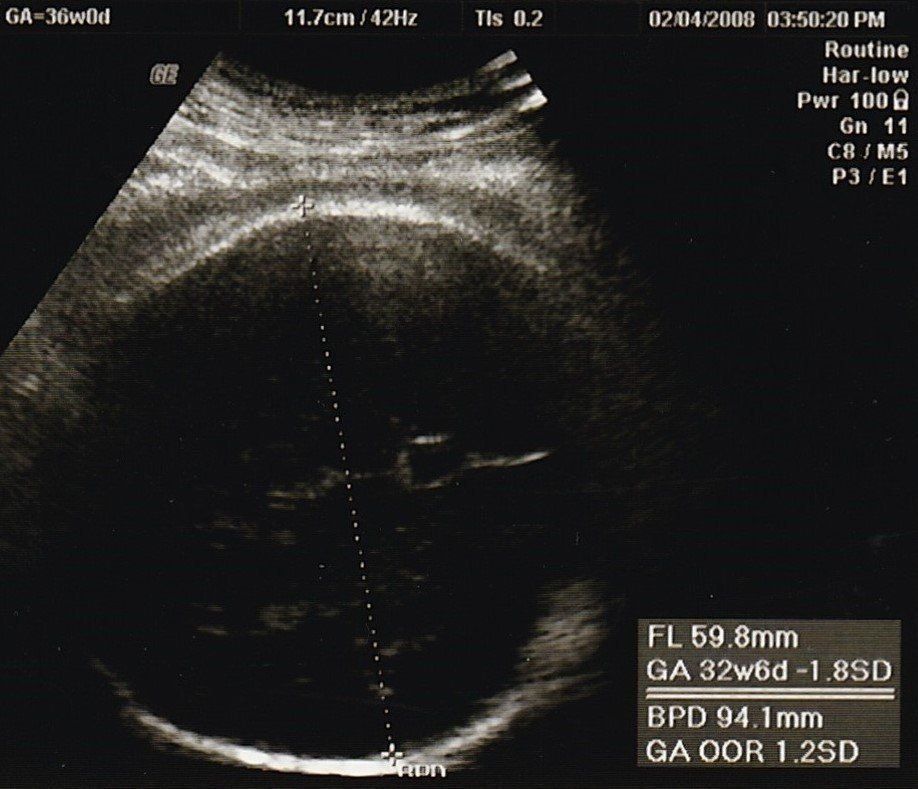

妊娠36週目のエコー写真

産院では、輸血が必要になったときのために、希望者は事前に自己採血し、院内保管してくれるということで、私は念のため希望しました。「たまごクラブ」や産院でもらった資料にある「入院準備のリスト」を見ながらチェックしました。